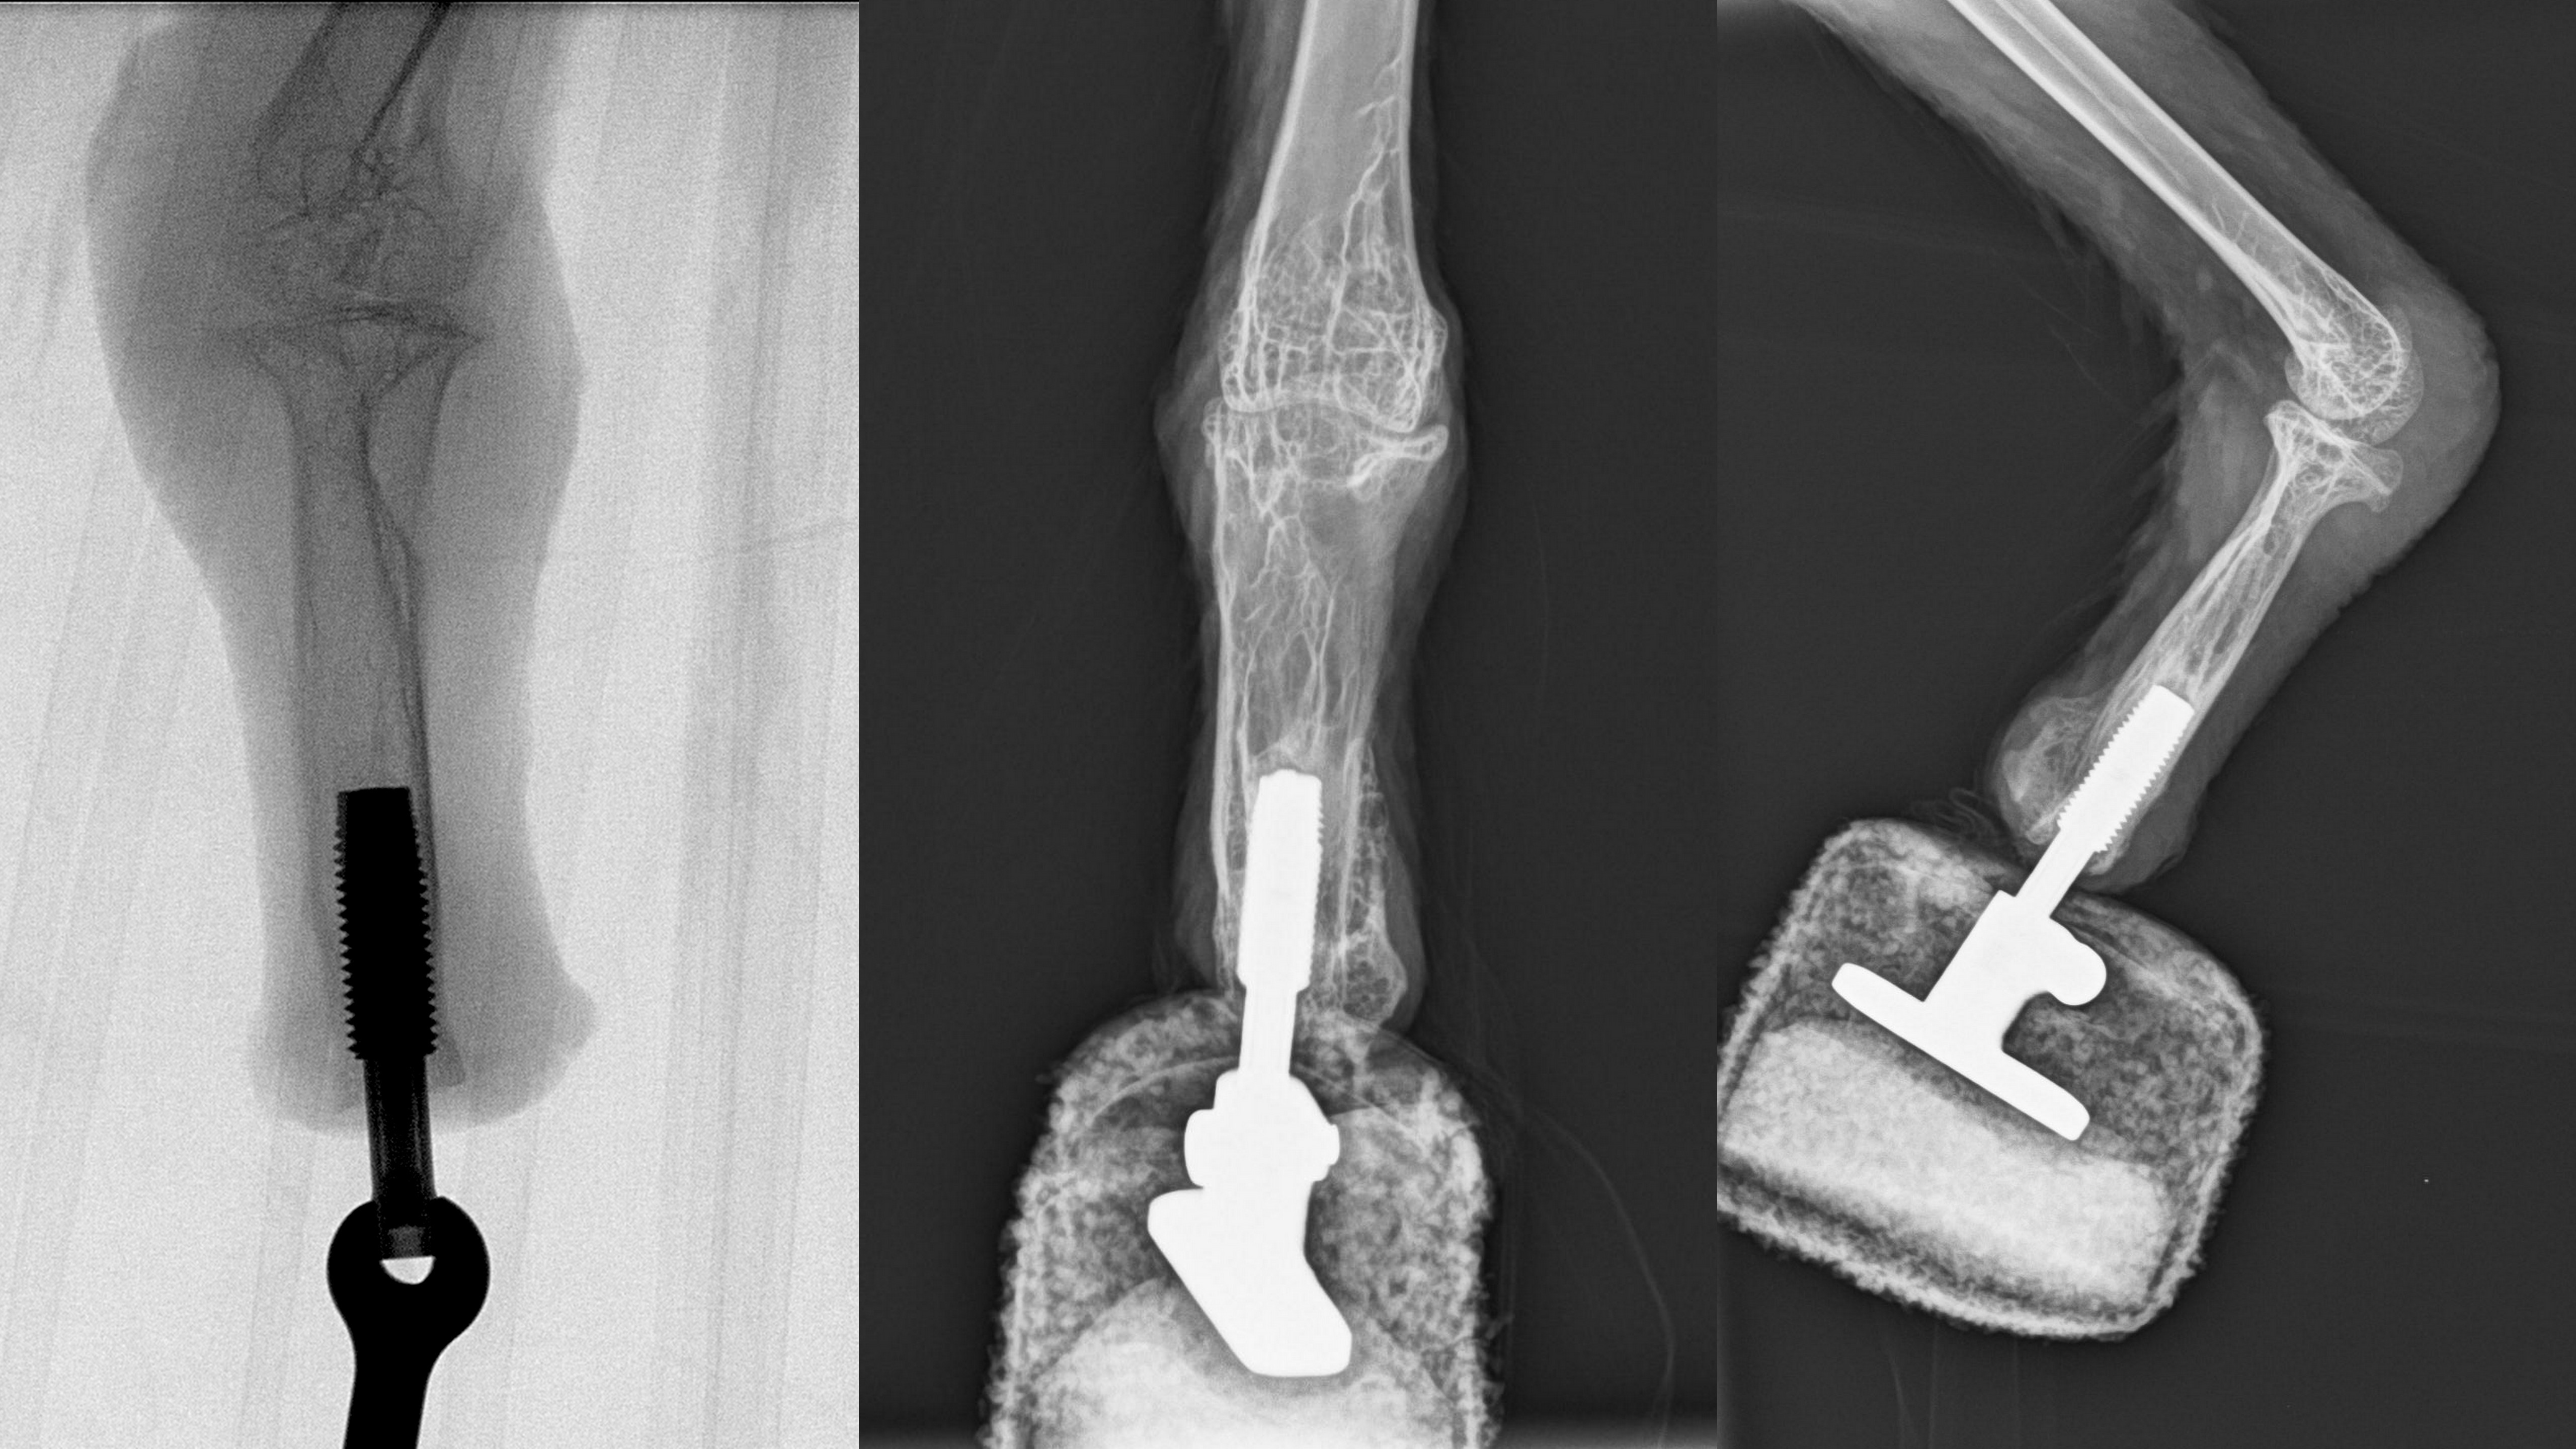

This new technique is known as osseointegration and Aszmann's working group recently used it for the first time in Austria on a patient who had lost an arm – however, it had never previously been attempted on a bird. In osseointegration, external parts of the prosthesis are directly connected to a bone anchor to guarantee a solid skeletal attachment. Aszmann explains: "This concept offers a high degree of embodiment, since osseoperception provides direct intuitive feedback, thereby allowing natural use of the extremity for walking and feeding. For the first time we have now successfully bionically reconstructed the limb of a vulture."

The operation on the bearded vulture was successfully carried out, together with Rickard Branemark from the Center for Osseointegration Research (San Francisco), at the Center for Biomechanical Research at MedUni Vienna (Director: Bruno Podesser). Rehabilitation and prosthetic treatment took place back in Haringsee. "The bird made the first attempts to walk after just three weeks and the prosthesis was under full load after six weeks. Today the bearded vulture can once again land and walk using both feet, making it the first 'bionic bird'," says Aszmann, who is famous throughout the world for his ground-breaking work on bionic hands.